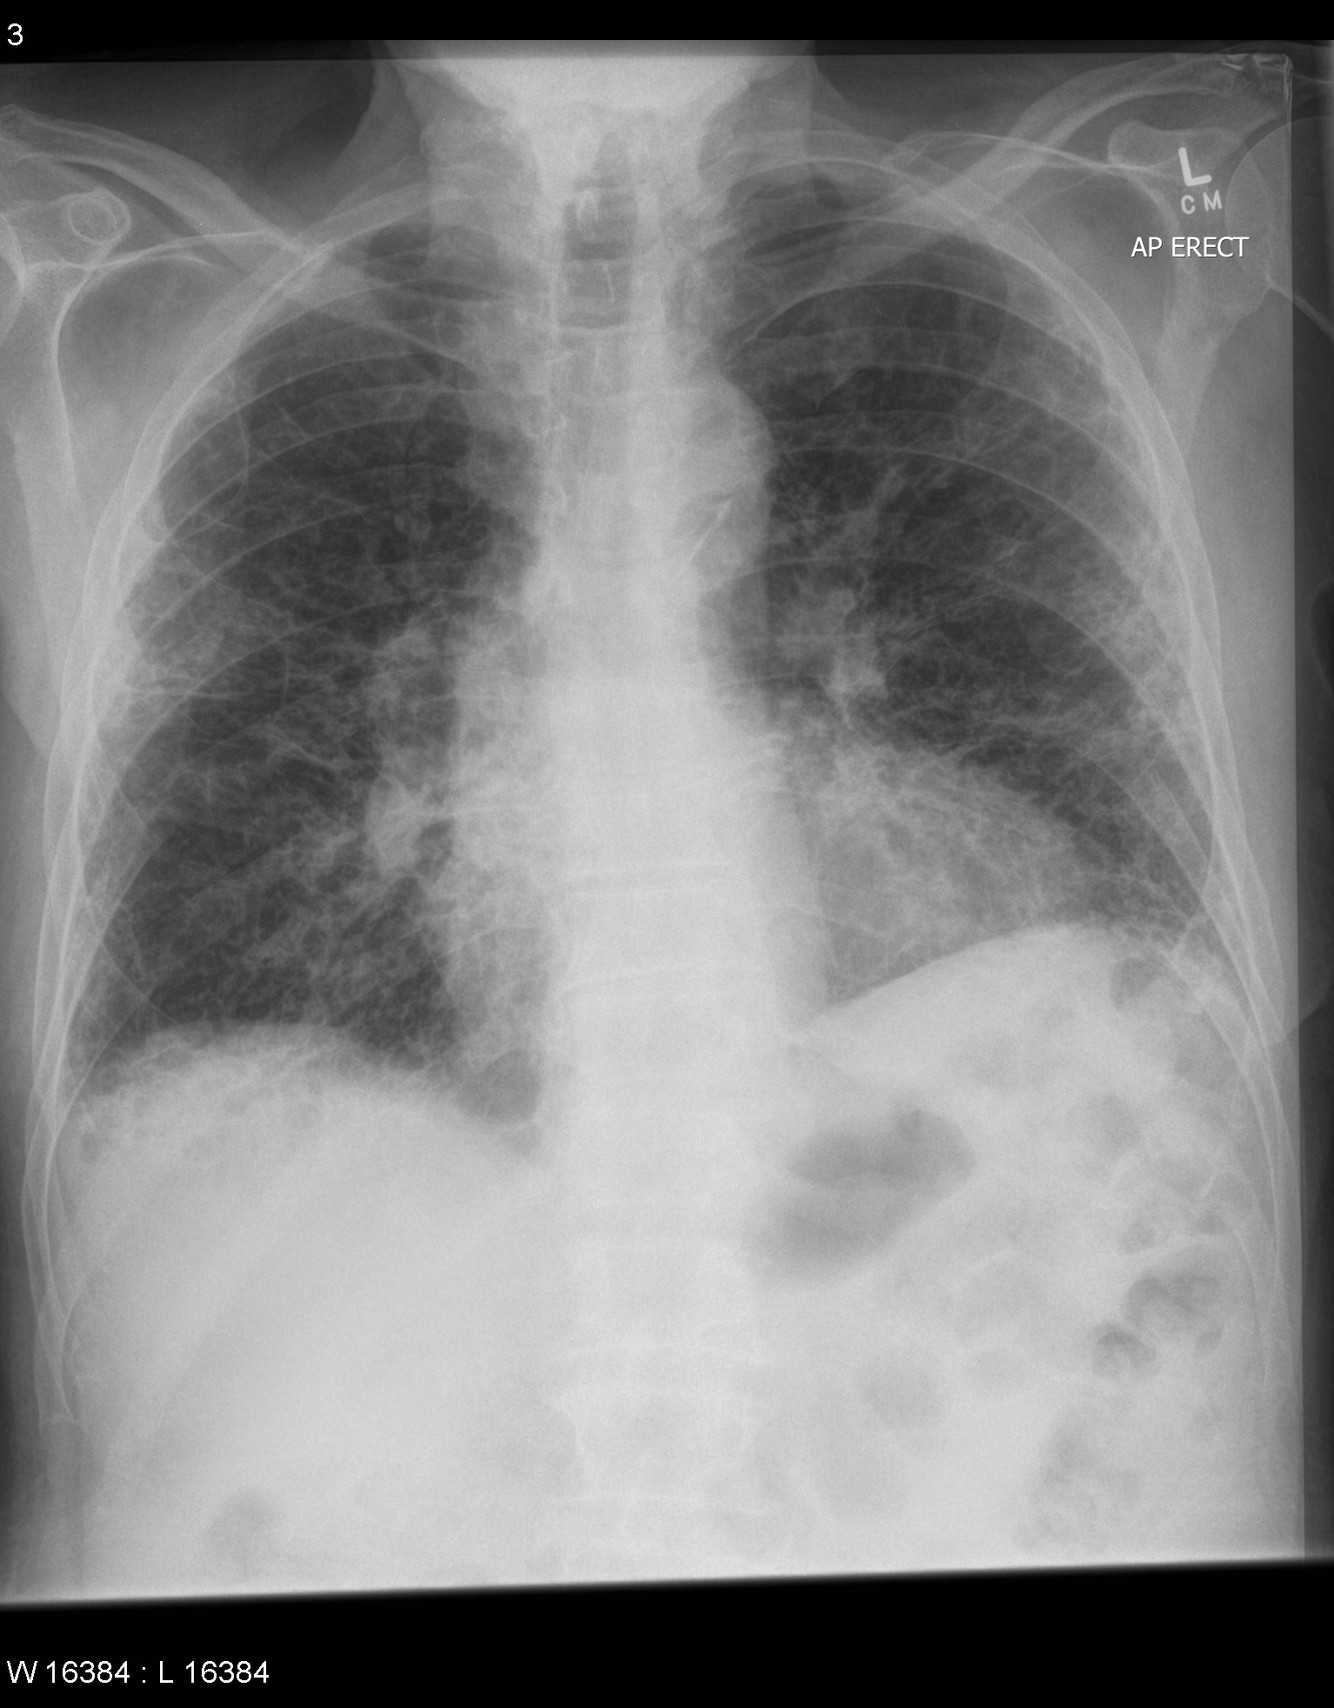

CXR: Lower Zone Fibrosis

DDx: